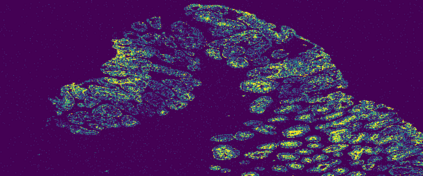

The usage of chemical imaging technologies is becoming a routine accompaniment to traditional methods in pathology. Significant technological advances have developed these next generation techniques to provide rich, spatially resolved, multidimensional chemical images. The rise of digital pathology has significantly enhanced the synergy of these imaging modalities with optical microscopy and immunohistochemistry, enhancing our understanding of the biological mechanisms and progression of diseases. Techniques such as imaging mass cytometry provide labelled multidimensional (multiplex) images of specific components used in conjunction with digital pathology techniques. These powerful techniques generate a wealth of high dimensional data that create significant challenges in data analysis. Unsupervised methods such as clustering are an attractive way to analyse these data, however, they require the selection of parameters such as the number of clusters. Here we propose a methodology to estimate the number of clusters in an automatic data-driven manner using a deep sparse autoencoder to embed the data into a lower dimensional space. We compute the density of regions in the embedded space, the majority of which are empty, enabling the high density regions to be detected as outliers and provide an estimate for the number of clusters. This framework provides a fully unsupervised and data-driven method to analyse multidimensional data. In this work we demonstrate our method using 45 multiplex imaging mass cytometry datasets. Moreover, our model is trained using only one of the datasets and the learned embedding is applied to the remaining 44 images providing an efficient process for data analysis. Finally, we demonstrate the high computational efficiency of our method which is two orders of magnitude faster than estimating via computing the sum squared distances as a function of cluster number.